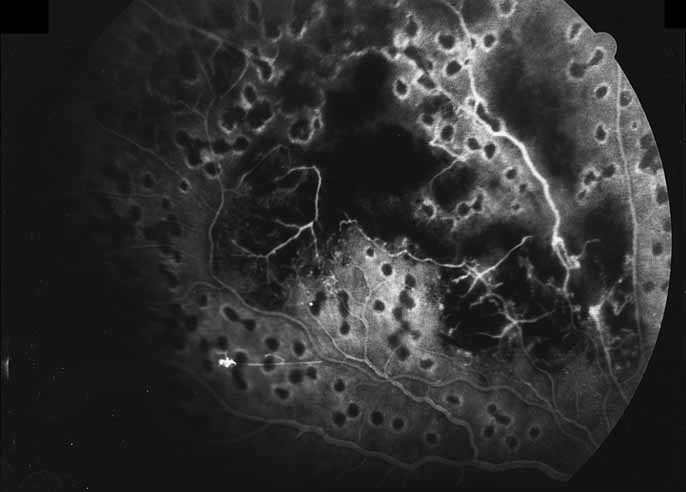

Fig. 28 Serpiginous choroiditis. ICG angiography early frame shows multiple hypofluorescent spots in the location of the lesions seen on color photography.

Fig. 29 Serpiginous choroiditis. ICG angiography later frame shows multiple hypofluorescent spots in the location of the lesions seen on color photography.